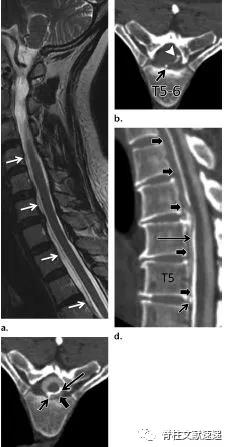

3.症状性胸椎间盘突出

- 在CT脊髓造影或MR成像中,当突出占椎管40%以上时,称为巨大突出。这些巨大的胸椎间盘突出症通常有密集的钙化,并有侵蚀硬脑膜的倾向。20%的人为无症状的胸椎间盘突出。有症状的胸椎间盘突出,尤其是需要手术的胸椎间盘突出少见。

- 对于有症状的胸椎间盘突出症,最常见的表现是疼痛。局限性疼痛的发生率与轴性疼痛相似,均大于根性疼痛的发生率。大约60%的患者出现脊髓病伴运动障碍,反射亢进或痉挛,感觉障碍的临床表现。膀胱功能障碍不太常见。脊髓病很少是急性的。当椎间盘巨大时,脊髓病的发生率显著增加。

图注:64岁女性,硬膜内胸椎间盘突出症,表现为进行性胸背痛和脊髓损害症状。术中见椎间盘骨赘复合体与硬脑膜紧密粘连。病理组织学检查示椎间盘组织和纤维化伴局灶性炎症改变。